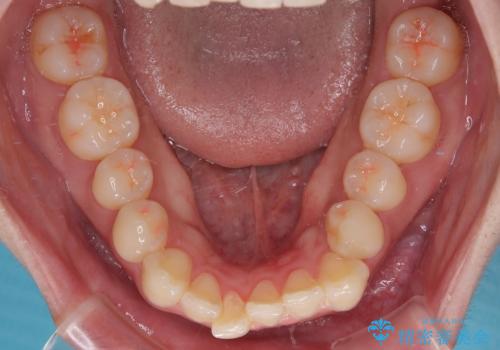

- 今回は「下の前歯のデコボコを治したい」と来院された患者様の症例をご紹介します。

診察してみると、下の前歯が並ぶためのスペースが足りないことが、歯並びがデコボコしている原因でした。

下の前歯の歯と歯の間をわずかに削ってスペースを作る(IPR)

奥歯を後ろに動かして、前歯が並ぶためのスペースを確保する

この計画により、デコボコだった下の前歯はしっかりと並び、わずか1年で治療を終えることができました